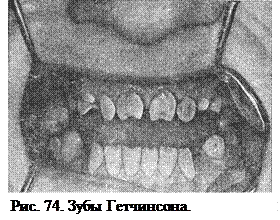

Зубы Гетчинсона, Фурнье. Гетчинсон описал особую форму центральных резцов с полулунной вырезкой режущего края, как признак врожденного сифилиса. Одно время этот взгляд оспаривался (рис. 74). Сам Гетчинсон признает этот признак при наличии, по крайней мере, еще двух признаков из триады – это паренхиматозный кератит и глухота.